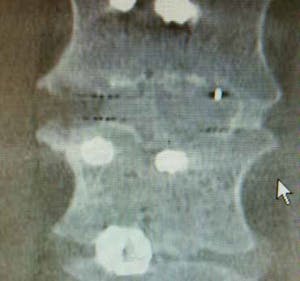

Radiolucency Minimal beam hardening Clear post-op imaging

While titanium provides high strength, PEEK-OPTIMA™ offers sufficient strength along with a bone-like modulus, reducing stress shielding and promoting better load sharing. Its radiolucency enables surgeons to assess fusion progress using X-ray or CT and MRI without the image artefacts caused by metal. PEEK-OPITMA™ HA Enhanced grades support bone ongrowth throughout the entire implant surface giving the Osseo-integrative bone bonding benefits of titanium combined with the benefits of PEEK.

PEEK-OPTIMA™ combines biocompatibility with mechanical properties that closely match cortical bone, including reducing stress shielding. It is also radiolucent, enabling clear post-operative imaging without interference. The material has a 20+ year clinical history, with approximately 15 million devices implanted worldwide and zero material-related recalls. Its stability, non-reactivity during clinical use, and absence of cytotoxicity make it highly reliable for long-term implantation

Invibio provides PEEK-OPTIMA™ polymers for implants that restore mobility and support bone integration in spinal and joint procedures. These materials combine mechanical strength with radiolucency for precise surgical assessment.